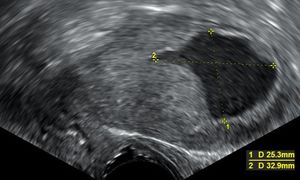

자궁내막암이 발견되면 암의 확산 및 조직 침범 여부를 확인하기 위해 의료 영상 검사를 수행한다. 2024년 연구에 따르면 질식 초음파 검사는 근층 침윤 평가에 있어 자기 공명 영상(MRI)과 유사한 진단적 성능을 제공하지만, MRI는 저등급 자궁내막암에서 더 나은 특이성을 보였다.[37]폐경기 출혈이 있는 여성의 경우, 질식 초음파 검사를 통해 자궁내막 두께를 검사하는 방법이 자궁내막암 진단에 많이 사용된다. 영국에서는 자궁내막 생검과 질식 초음파 검사를 함께 사용하는 것이 표준 진단법이다. 질식 초음파 검사에서 보이는 조직의 균질성은 암성 여부를 판단하는 데 도움이 되지만, 초음파 소견만으로는 결정적이지 않으므로 자궁내막 생검과 같은 다른 검사 방법을 함께 사용해야 한다.

폐경기 출혈이 있는 여성의 자궁내막 두께를 검사하기 위한 질식 초음파 검사는 미국에서 자궁내막암 진단을 돕기 위해 점점 더 많이 사용되고 있다.[37] 영국에서는 자궁내막 생검과 질식 초음파 검사를 함께 사용하는 것이 자궁내막암 진단의 표준 치료법이다.[35] 질식 초음파 검사에서 보이는 조직의 균질성은 두께가 암성인지 여부를 나타내는 데 도움이 될 수 있다. 초음파 소견만으로는 자궁내막암의 경우 결정적이지 않으므로 다른 선별 검사 방법(예: 자궁내막 생검)을 함께 사용해야 한다. 다른 영상 검사는 제한적으로 사용된다. CT 스캔은 신체 검사에서 진행된 것으로 보이거나 고위험 아형(전이 위험이 높은)을 보이는 종양의 수술 전 영상 검사에 사용된다.[38] 또한 골반 외 질환을 조사하는 데에도 사용할 수 있다.[35] MRI는 암이 자궁 경부로 전이되었는지 또는 자궁 경부 선암종인지 확인하는 데 어느 정도 도움이 될 수 있다.[38] MRI는 또한 인접 림프절을 검사하는 데 유용하다.[35]